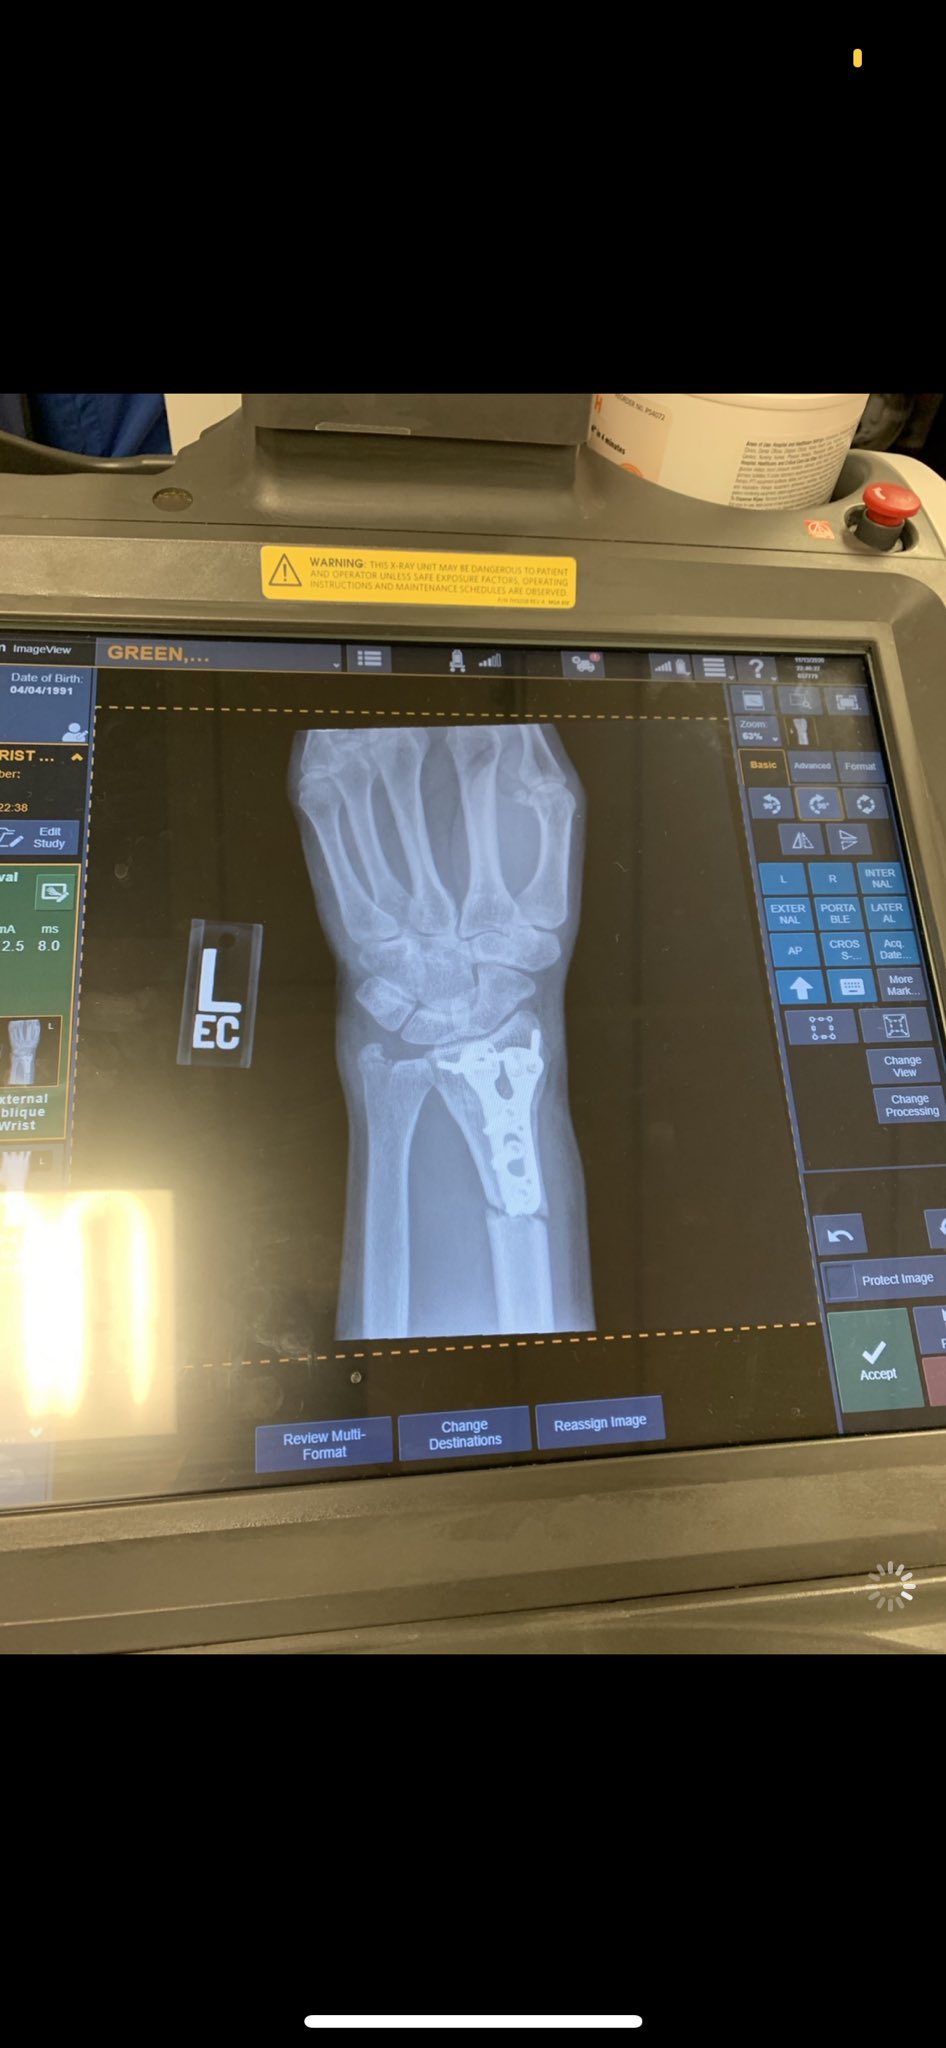

She also uploaded a couple of images of her arm, which shows a very nasty scar on her wrist. A picture of her fractured x-ray arm was also posted by her. The caption of the photos stated,

“Wow the last month has gone by QUICK… Every day my arm gets stronger, my rehab gets easier, and I’m closer to making my (6th?) @WWE main roster debut.”